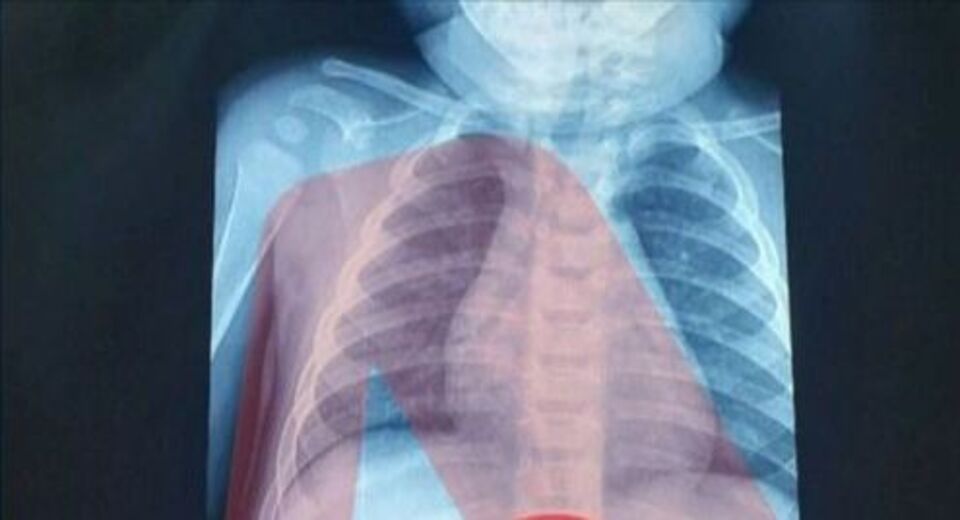

Ένας 3χρονος μεταφέρθηκε εσπευσμένα στο νοσοκομείο, το οποίο κατάπιε ένα ξυραφάκι. Το παιδί αφού έφτασε σε Παίδων της Αθήνας, υποβλήθηκε άμεσα σε ακτινογραφία, η οποία έδειξε ότι όντως υπήρχε το αιχμηρό αντικείμενο στο στομάχι του

Όπως ενημέρωσαν οι γιατροί, τους γονείς του παιδιού, μετά την ακτινογραφία προσδιορίστηκε και το ακριβές σημείο όπου βρέθηκε το ξυραφάκι, ώστε οι χειρουργοί να προχωρήσουν σε επέμβαση αφαίρεσής του με ασφάλεια.